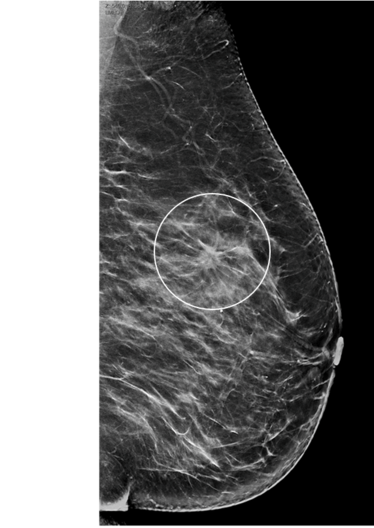

Systematische Brustkrebs-Früherkennung mit Digitaler Brust-Tomosynthese (DBT) und synthetischer 2D-Bildgebung (Foto: UKM-Radiologie Münster)

Die hohe Zahl der teilnehmenden Frauen belegt nach den Worten von Studienleiter Prof. Dr. Walter Heindel die hohe Akzeptanz der systematischen Brustkrebs-Früherkennung im deutschen Screening-Programm. Der Direktor der Klinik für Radiologie und Leiter des Referenzzentrums Mammographie am Universitätsklinikum Münster (UKM) berichtet von weltweit hohen Erwartungen an die Studie. Die Weiterentwicklung der digitalen Mammographie zur Brust-Tomosynthese biete eine Technologie, die, so der Radiologe, „durch die Berechnung dreidimensionaler Datensätze potentielle Gewebeüberlagerungen in der Brust reduziert und die daher diagnostische Vorteile ermöglichen kann“. Im ersten Schritt will die Forschungsgruppe den Kenntnisstand einer gesteigerten Brustkrebsdetektion im Screening beurteilen. Konkret bedeutet das: Was kann im Sinne der Frauen zusätzlich erreicht werden, was das 2D-Mammographie-Screening vorher nicht konnte? Als zweite Hypothese wird die Quote von Mammakarzinomen unter Frauen in einem Zeitraum von zwei Jahren nach Screening-Teilnahme zwischen der Tomosynthese-Testgruppe und der Kontrollgruppe verglichen.